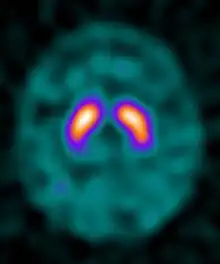

Ioflupane (123I) is the international nonproprietary name (INN) of a cocaine analogue which is a neuro-imaging radiopharmaceutical drug, used in nuclear medicine for the diagnosis of Parkinson's disease and the differential diagnosis of Parkinson's disease over other disorders presenting similar symptoms. During the DaT scan procedure it is injected into a patient and viewed with a gamma camera in order to acquire SPECT images of the brain with particular respect to the striatum, a subcortical region of the basal ganglia.[7] The drug is sold under the brand name Datscan and is manufactured by GE Healthcare, formerly Amersham plc.

Ioflupane has a high binding affinity for presynaptic dopamine transporters (DAT) in the brains of mammals, in particular the striatal region of the brain. A feature of Parkinson's disease is a marked reduction in dopaminergic neurons in the striatal region. By introducing an agent that binds to the dopamine transporters a quantitative measure and spatial distribution of the transporters can be obtained.